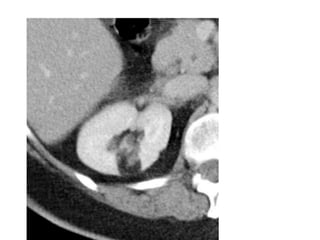

• #36 high signal intensity on non-fat saturated sequences, and loss of signal following fat saturation Renal angiomyolipomas (AMLs) are a type of benign renal neoplasm and are composed of vascular, smooth muscle and fat elements.